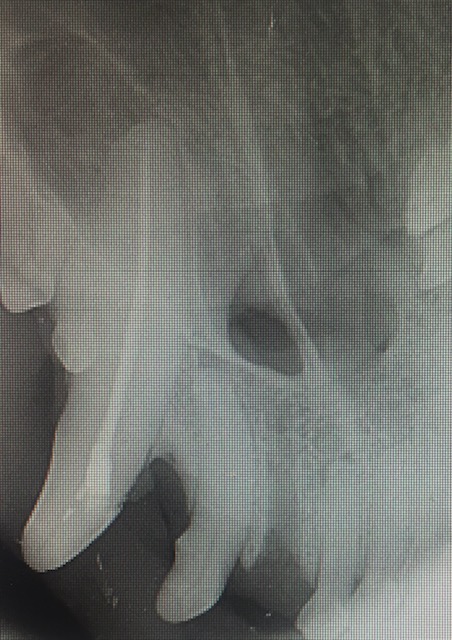

As you can see in the photos the canine tooth is massive. The crown, which is the part that extends into the mouth, is only a small part of this tooth. The root is large and held in the jaw by very a strong periodontal ligament that has fibres running from the tooth to the surrounding bone.

For an extraction, a large gingival flap is made and alevolar bone is burred away. The amount of bone burred away will be less if a vet-tome instrument is used. The tooth is then elevated and luxated out of the socket. When teeth are fractured (as opposed to periodontally diseased), the tooth is normally structurally sound so extraction of the tooth does require a fair amount of force. It is relatively traumatic. Post extraction the socket is flushed with saline and the gingival flap sutured closed. It is important the dog eats soft food and does not chew on anything hard while the gum is healing as wound breakdown can occur and the dog animal may need another anesthetic for resuturing the gingival flap.